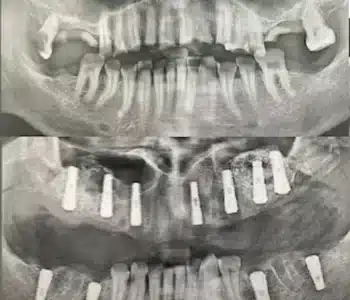

Dr. Seden Aksu is a specialist in modern implantology and surgical dentistry with extensive experience in the management of complex clinical cases. In her practice, she applies comprehensive surgical planning, minimally invasive techniques, and advanced regenerative technologies aimed at restoring both the function of the dentoalveolar system and the aesthetics of the smile. Dr. Aksu has significant experience in performing implant procedures, bone augmentation, and periodontal surgery, including the treatment of patients with severe bone loss. The primary goal of her work is to achieve stable, long-term outcomes in implant rehabilitation and the restoration of oral tissue health.